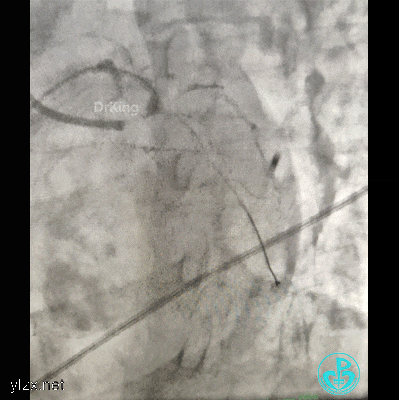

植入4.0×13mm支架1枚。

交换导丝后扩支架网眼。